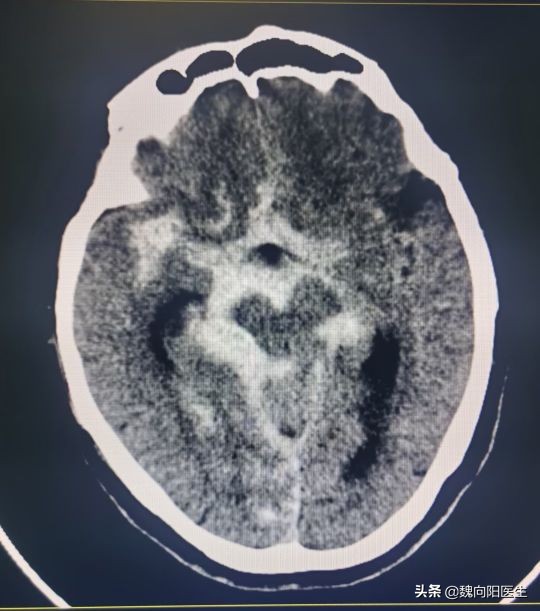

赶紧拉到医院,头CT提示:蛛网膜下腔出血。

这可是一个要命的病,一般都是由于脑动脉瘤破裂所导致。

动脉瘤破裂之后,会涌出大量的新鲜血液,使大脑浸泡在血水当中。随时间的推移,这些血水会持续的毒害大脑,导致一系列的反应。

正常人的脑积液属于无色透明的,蛛网膜下腔出血之后,血液涌到脑室里面和蛛网膜下腔,与脑积液混合就会变成血红色。

脑脊液充满于大脑的表面、侧脑室、第四脑室、第三脑室、椎管内脊髓的表面和腰椎管内。